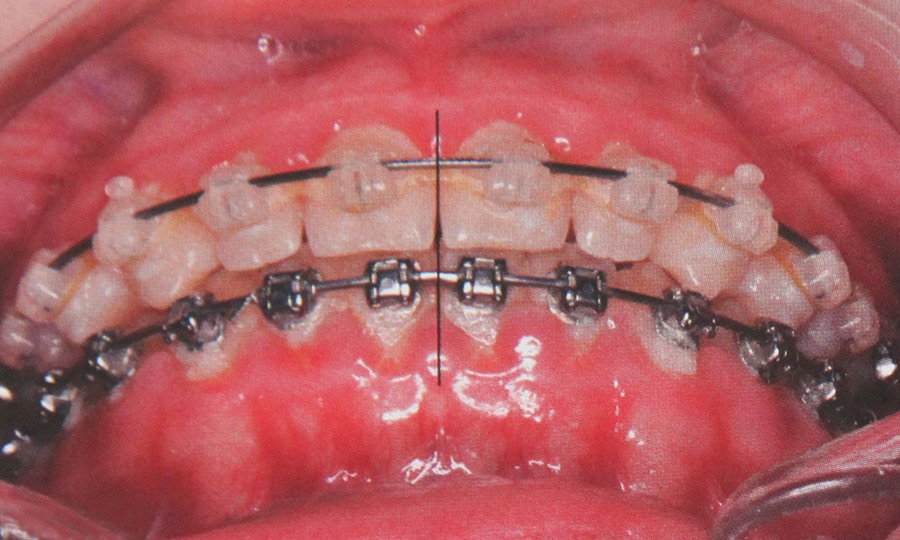

Aparatele fixe sunt alcatuite din bracheti aplicate pe fiecare dinte si o succesiune de arcuri ce asigura alinierea dintilor. Aceste bracheti pot fi metalici sau ceramici alternative pentru cei care nu vor ca aparatele sa fie vizibile.